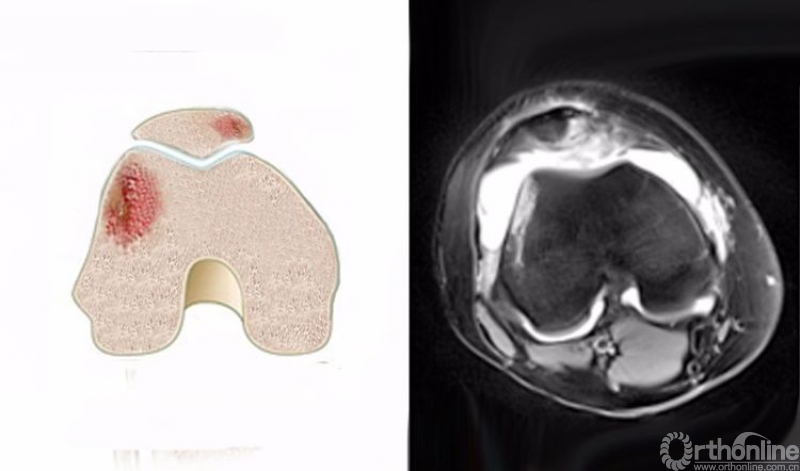

5.髌骨脱位(patellar dislocation)

髌骨脱位是一种常见的损伤,其损伤是短暂性的,病人不一定意识到,而在体检时由于肿胀和疼痛而影响检查,因此有50%-70%的患者在初次就诊时不能获得诊断。

髌骨脱位是髌骨内侧与股骨外髁外侧壁发生撞击,在MRI上主要表现为髌骨内侧及股骨外髁外侧壁的骨髓水肿,T2WI及STIR像呈高信号改变。可合并内侧髌股副韧带撕裂、髌骨及其股骨外髁的骨软骨损伤。